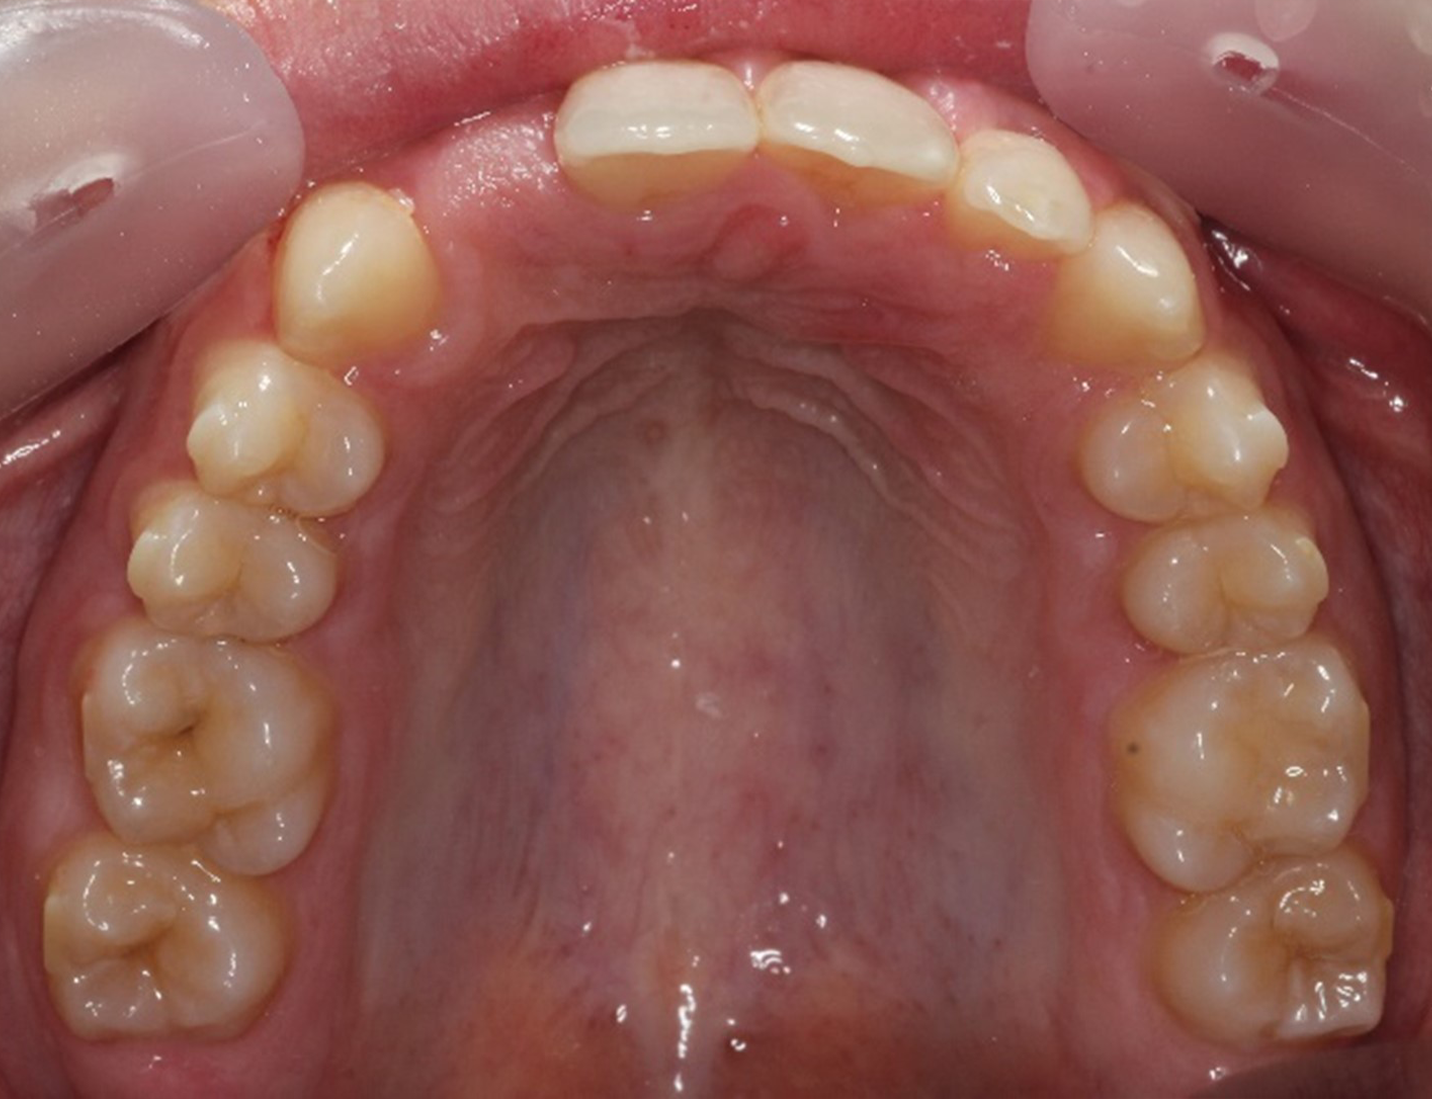

Upper arch: 20 active aligners

Transverse expansion

Derotation with mesial-out of first molars

Space opening for 12 by distalizing 13

Maxillary midline correction

This case demonstrates the accuracy and efficiency of Spark Aligners in:

Spark provided predictable movements, excellent aligner fit, and precise finishing, enabling successful orthodontic outcomes and future prosthetic.